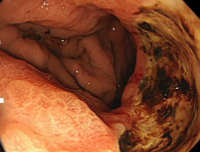

進行大腸がんです。

血便がきっかけで大腸内視鏡検査を行いました。

血便以外には全く症状がなく、静かに進行していたと考えられます。大学病院で外科的手術後に抗がん剤治療が必要でした。